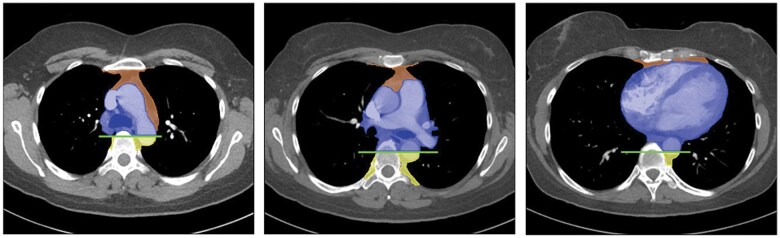

纵隔肿块是一组异质性的实体,具有多种组织病理学和放射学特征。影像学在纵隔异常的检测和解释中起着关键作用。CT仍然是首选的方式,因为它具有高空间和时间分辨率,并且能够评估组织组成,包括检测液体、脂肪和钙化。MRI在特定情况下是一种辅助工具,如区分复杂囊肿和实性病变或识别细胞内脂肪含量,如胸腺增生。纵隔肿块的鉴别诊断主要依赖于肿块的位置和组织组成,并结合患者的临床特征。这篇综述讨论了成人最常见的纵隔肿块,提供了一种主要基于优势密度模式和位置的实用方法来区分它们。

Mediastinal masses represent a heterogeneous group of entities characterized by a variety of histopathological and radiological features. Imaging plays a pivotal role in the detection and interpretation of mediastinal abnormalities. CT remains the modality of choice due to its high spatial and temporal resolution and its ability to assess tissue composition, including the detection of fluid, fat, and calcifications. MRI represents a complementary tool in specific scenarios, such as differentiating complicated cysts from solid lesions or identifying intracellular fat content, as seen in thymic hyperplasia. The differential diagnosis of mediastinal masses relies primarily on the location of the mass and tissue composition, integrated with clinical characteristics of the patient. This review discusses the most common mediastinal masses in adults, providing a practical approach to their differentiation mainly based on the predominant density pattern and location.